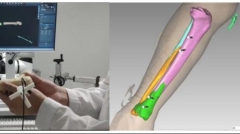

下肢骨折复位固定一体化手术机器人系统成果简介

发布:中医药创新转化研究院